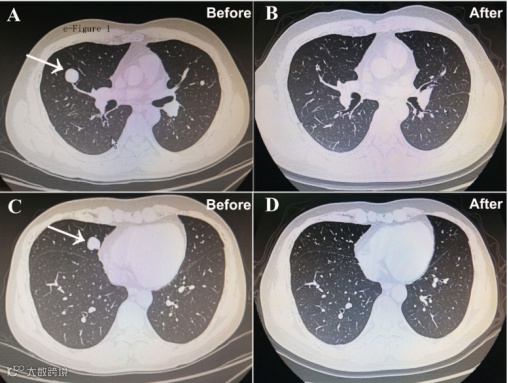

此次发布的研究是一项由上海东方肝胆外科医院程树群教授和石洁教授牵头的全国多中心、双盲、随机、安慰剂对照临床试验,纳入的患者均为晚期肝癌伴有远处转移,按1:1比例随机接受了全反式维甲酸联合FOLFOX4或者安慰剂联合FOLFOX4治疗。结果显示全反式维甲酸联合FOLFOX4治疗组的客观缓解率为24.5%,中位生存时间延长至16.2个月,显著高于安慰剂联合FOLFOX4治疗组的9.1%和10.7个月 (p值分别为0.031和0.025)。安全性分析结果显示两组不良反应发生率无统计学差异,证明了全反式维甲酸联合FOLFOX4是安全的。

靶向及免疫治疗是近年来晚期肝癌远处转移的首选方法,但是有效率低,大部分患者对靶向及免疫治疗不敏感。本研究的亚组分析显示,即使对于既往接受过靶向或免疫治疗的晚期肝癌远处转移患者,全反式维甲酸联合FOLFOX4治疗组仍显示出较好的疗效。文中还对全反式维甲酸联合FOLFOX4的疗效预测进行了蛋白组学分析,找到了化疗敏感(完全缓解或部分缓解)的标志物可供进一步研究。